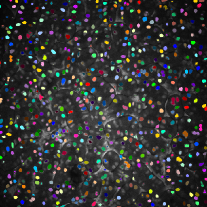

Figure 3 shows the synthetic images generated by our proposed method. The left column indicates original images whereas middle column shows synthetic images artificially generated from corresponding synthetic binary images provided in right column. As can be seen from Figure 3, the synthetic images reflect characteristics of the original microscopy images such as background noise, nuclei shape, orientation and intensity.

Additionally, two synthetic data generation methods between CycleGAN and SpCycleGAN from the same synthetic binary image are compared in Figure 4. Here, the synthetic binary image is overlaid on the synthetic microscopy image and labeled in red. It is observed that our spatial constraint loss reduces the location shift of nuclei between a synthetic microscopy image and its synthetic binary image. Our realistic synthetic microscopy volumes from SpCycleGAN can be used to train our modified 3D U-Net.